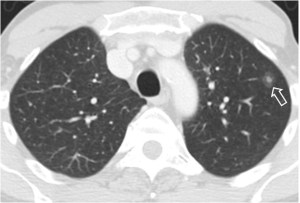

La presencia de una melladura o escotadura en el contorno de un nódulo pulmonar solitario se describió como un signo de malignidad. Si bien es cierto que es más frecuentemente visto en nódulos malignos, este signo puede verse también en lesiones benignas, por lo que no resulta útil. En la imagen vemos una escotadura (flecha) en un cáncer de pulmón.